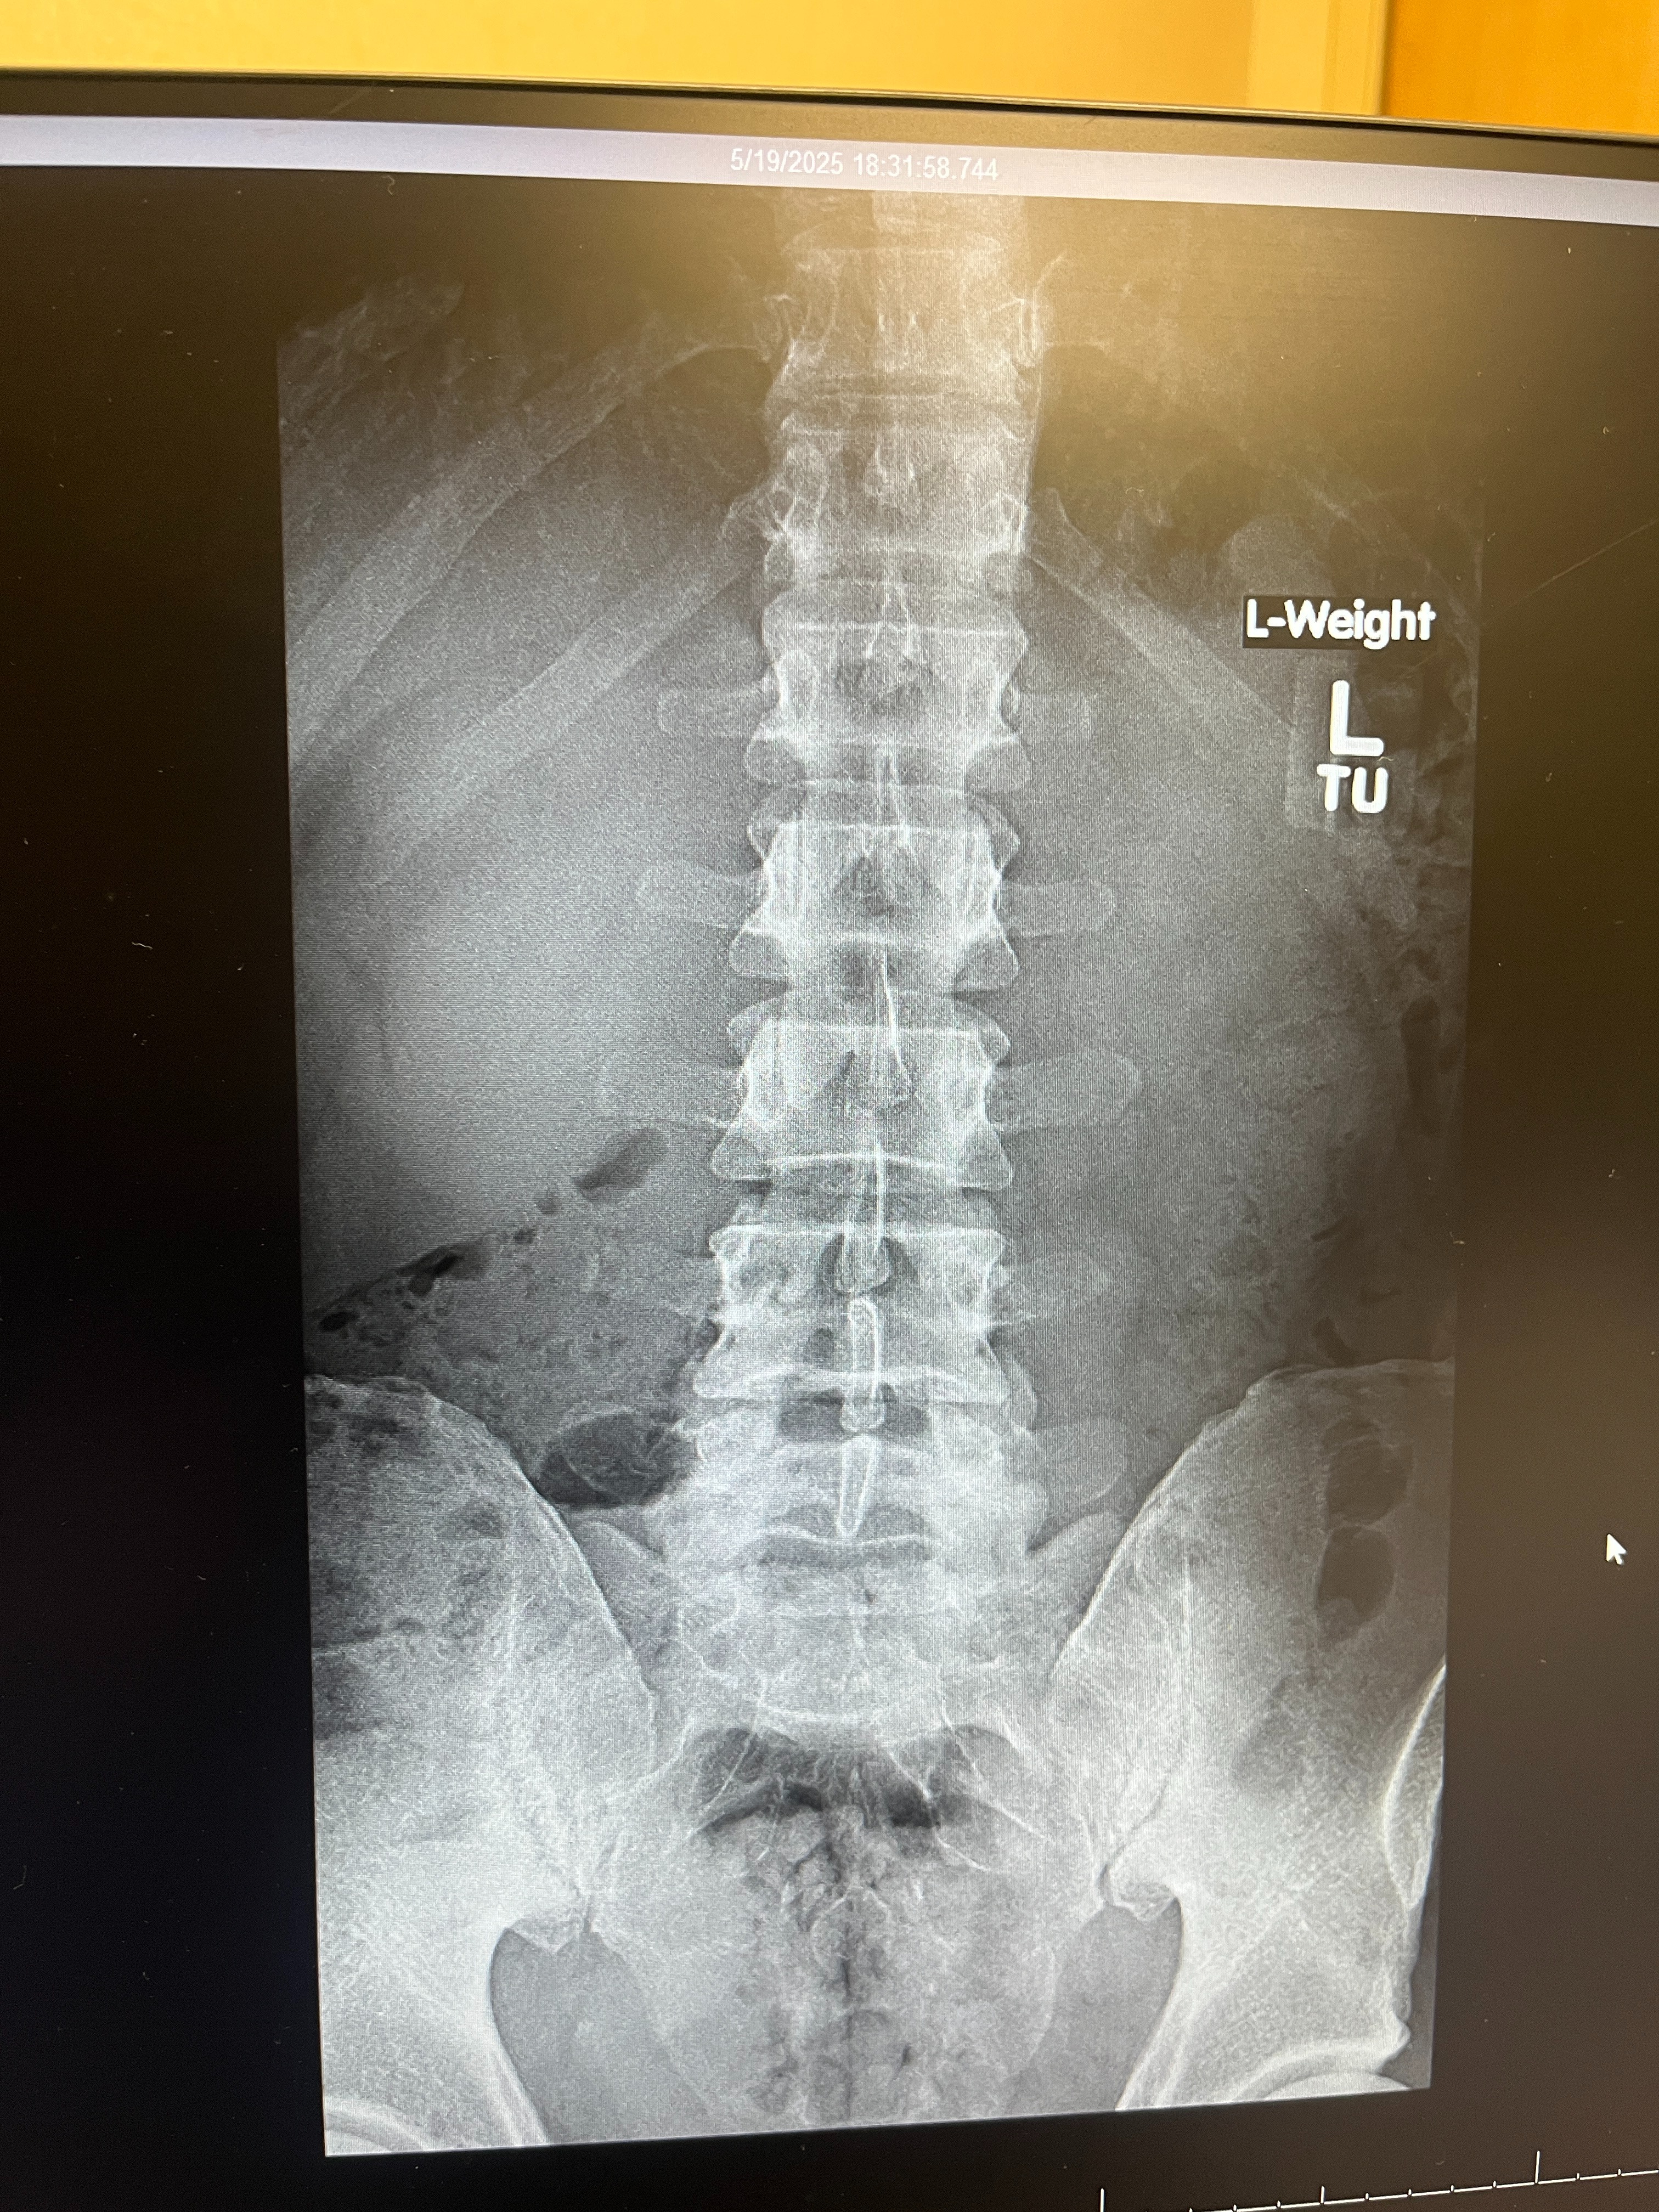

Hello Everyone, I'm in need of a spinal stem cell treatment to stop this injury from getting worse. I had a major spinal injury at the age of 26, and doctors have always told me that eventually I'd need back surgery, but, I did intense rehab and made healthy lifestyle choices over the years and stretched that time I feel as far as I could, however, I still don't want to go under the knife and have surgery. My close friends that have had spinal surgery all wish they didn't do it but at the time there wasn't an alternative, now there is one. I'm 40 years old now and I know a stem cell procedure is my best option to have my body heal itself. I have Spinal Stenosis, Degenerative Disc Disease and Disc Herniations. I've done rehabilitation. I eat right and take care of my body, but, nerve pain affects even the strong and healthy athletes, not just people who aren't athletic and not in shape. The pain from this is unbearable, and I'm currently not working because of this injury. I don't earn enough in order to attain this goal for this procedure, however, I've always been a hard worker and have career dreams and goals like anyone else. I always do my very best to achieve those dreams and goals, but as of right now my only focus is to get better. I need your help in order to do that. If you can, please donate and share this campaign with others, and if you cannot donate, I truly understand that and thank you so very much with all my heart and soul for your time. I do humbly ask however that you please pray for me regardless. I know that's more powerful than anything else. I do my best to build my relationship with GOD, and I'm very aware that my own sins have led me to where I currently am, and I have to truly repent and seek forgiveness for my choices and actions out of harmony with God's Love & Truth and loving Laws of the Universe. I continue to pray to receive God's Love and Truth into my soul to build my relationship with God and I pray you all one day desire the same. Thank you again for your time and your help. God Bless you all.